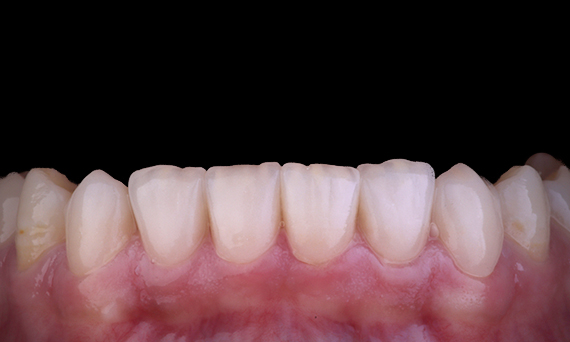

Il est assez courant d’observer des fissures et des fractures associées aux restaurations en amalgame, en particulier lorsqu’elles augmentent en taille, car il s’agit de restaurations « non collées ». Beaucoup de ces dents sont structurellement compromises et une approche adhésive et biomimétique est la méthode idéale pour restaurer ces dents. Dans le cadre d’un plan de traitement plus complet, ce quadrant devait recevoir deux onlays indirects en céramique. Les première et deuxième molaires ont été restaurées en une seule visite à l’aide du CEREC Tessera, un disilicate de lithium avancé.

Dr Yo-Han Choi, Sydney, Australie